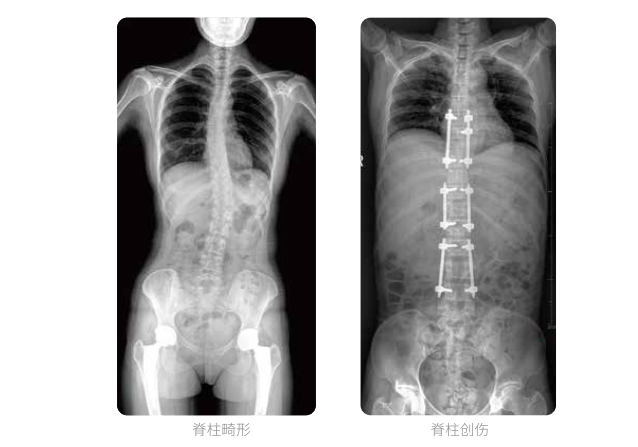

PLX8600大視野平板動態DR全脊柱一次成像攝片適用于兒童、成人、老年人腰椎退行性病變、強直性脊柱炎、脊柱結核等臨床應用,在此類大視野的臨床拍攝中發揮了極大的價值。

PLX8600大視野平板動態DR可在透視情況下多角度觀察病灶部位,做術前診斷及術后愈合的檢查,如脊柱斜位透視,可觀察椎弓根峽部,診斷椎體是否滑脫等情況;可在脊柱運動狀態下通過透視模式觀察全脊柱狀態,了解病變處脊柱的活動度及骨結構的關系,配合點片功能快速獲得高清的關鍵幀影像,輔助醫生制定更準確的手術方案。